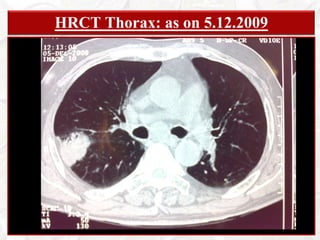

PATIENT  PARTICULARSKHAGEN BARUAH68 years; Male; HinduRetired Clerk from Assam State Electricity BoardAddress: Doom Dooma, Dist: Tinsukia, AssamBed: 88; Unit: Male Med Unit VDate of Admission: December 5th, 2008Date of Examination: December 14th, 2008